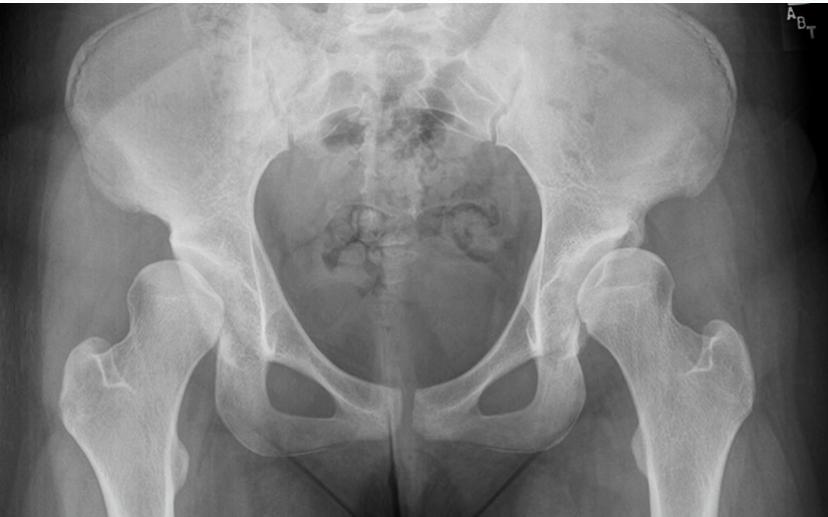

Case 3: 16-year-old, bilateral limping